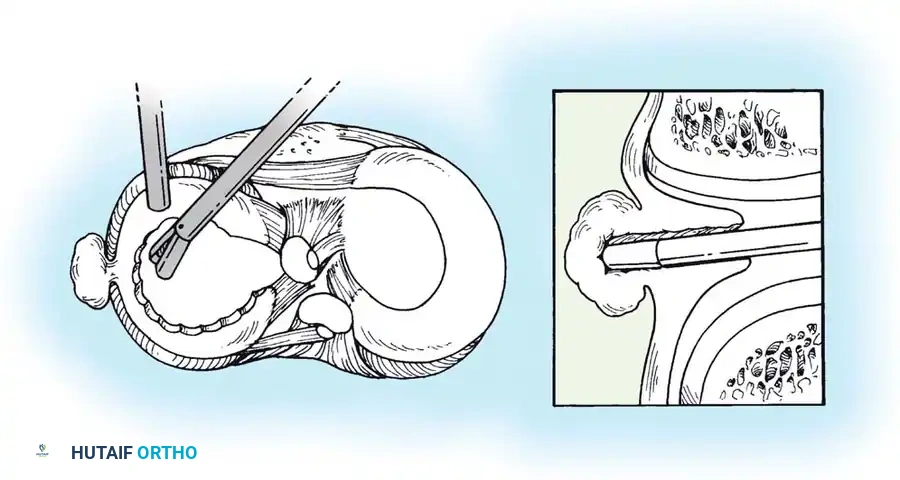

Transtibial Pull-Out Repair

- Debridement: The anatomic footprint of the root is decorticated to a bleeding bone bed using a shaver or curette.

- Suture Passing: Heavy, non-absorbable tapes are passed through the detached meniscal root using a specialized suture-passing device.

- Tunnel Creation: A tibial aiming guide is used to drill a tunnel from the anteromedial tibia to the anatomic root footprint.

- Fixation: The sutures are shuttled down the tibial tunnel and tied over a cortical button or secured with a bio-tenodesis screw on the anterior tibia.